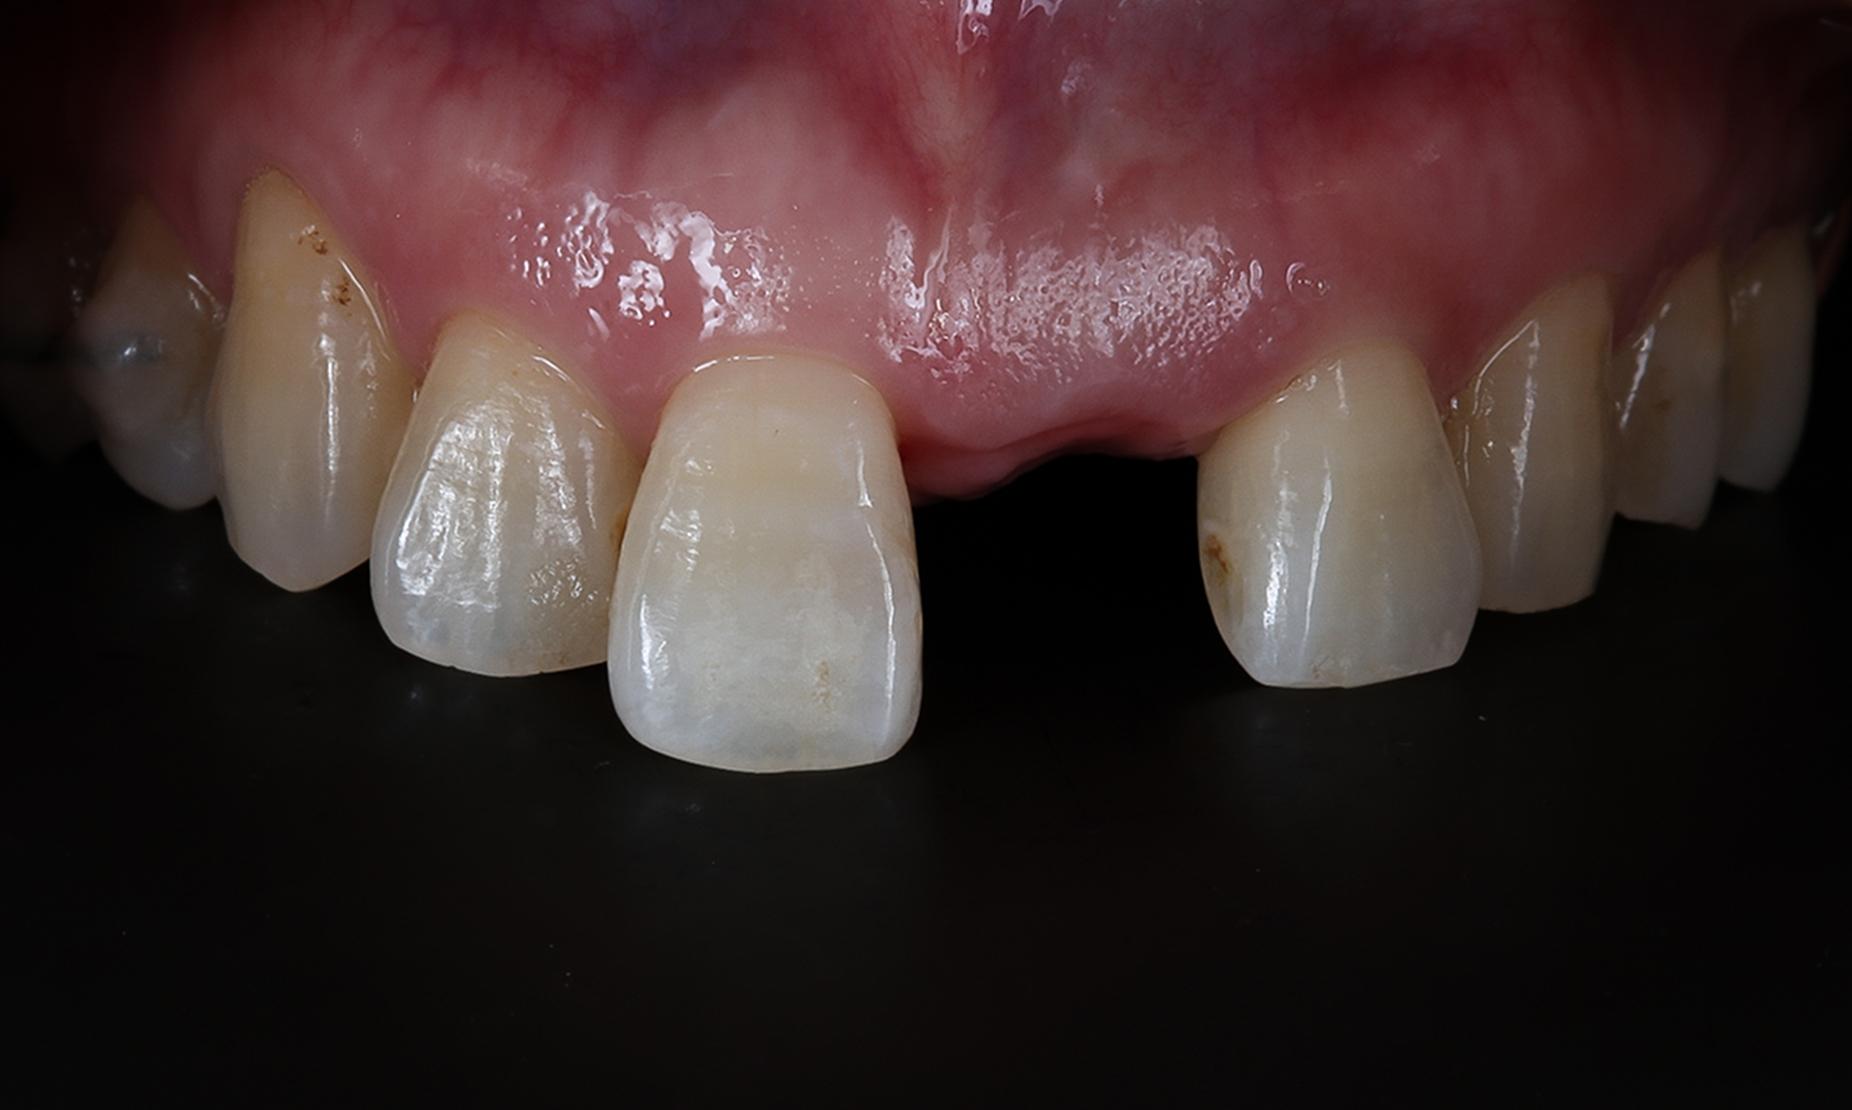

術後数週間で歯ぐきが十分に回復し、その後インプラントと骨が結合するまでの2〜3カ月間を使って、カスタムアバットメント(歯ぐきの形を整えるための仮歯)を使用して歯ぐきの形状を調整しました。このステップにより、自然な歯ぐきのラインを形成することが可能となります。安価なインプラントの場合、この手順が省略されてしまうことがしばしばあります。

歯ぐき形成用のカスタムアバットメント(インプラント仮歯)が入ったところ。

カスタムアバットメント。これで歯ぐきを圧迫して形成していく。

インプラントと骨がしっかりと結合した頃、立体的な歯ぐきの形成もできました。仮に結合組織移植術=歯ぐきの再生治療を行わなかった場合には、このような自然は歯ぐきの形成は難しくなります。

元の歯がここにあったことが思い浮かぶような歯ぐきの形に仕上がった。